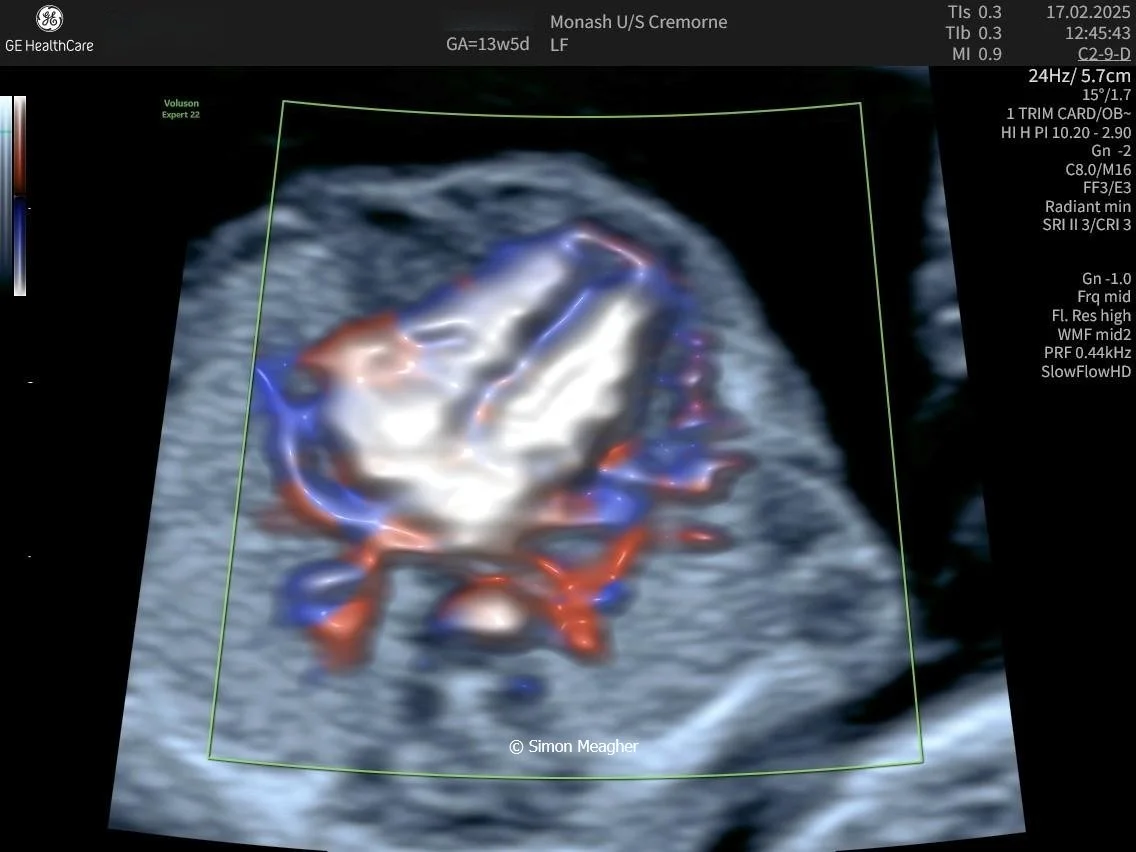

Join Professor Simon Meagher and leading experts for an intensive masterclass designed to transform your clinical practice.

This high-impact, one-day event delivers live scanning demonstrations, real-world case studies, and cutting-edge techniques across all trimesters.